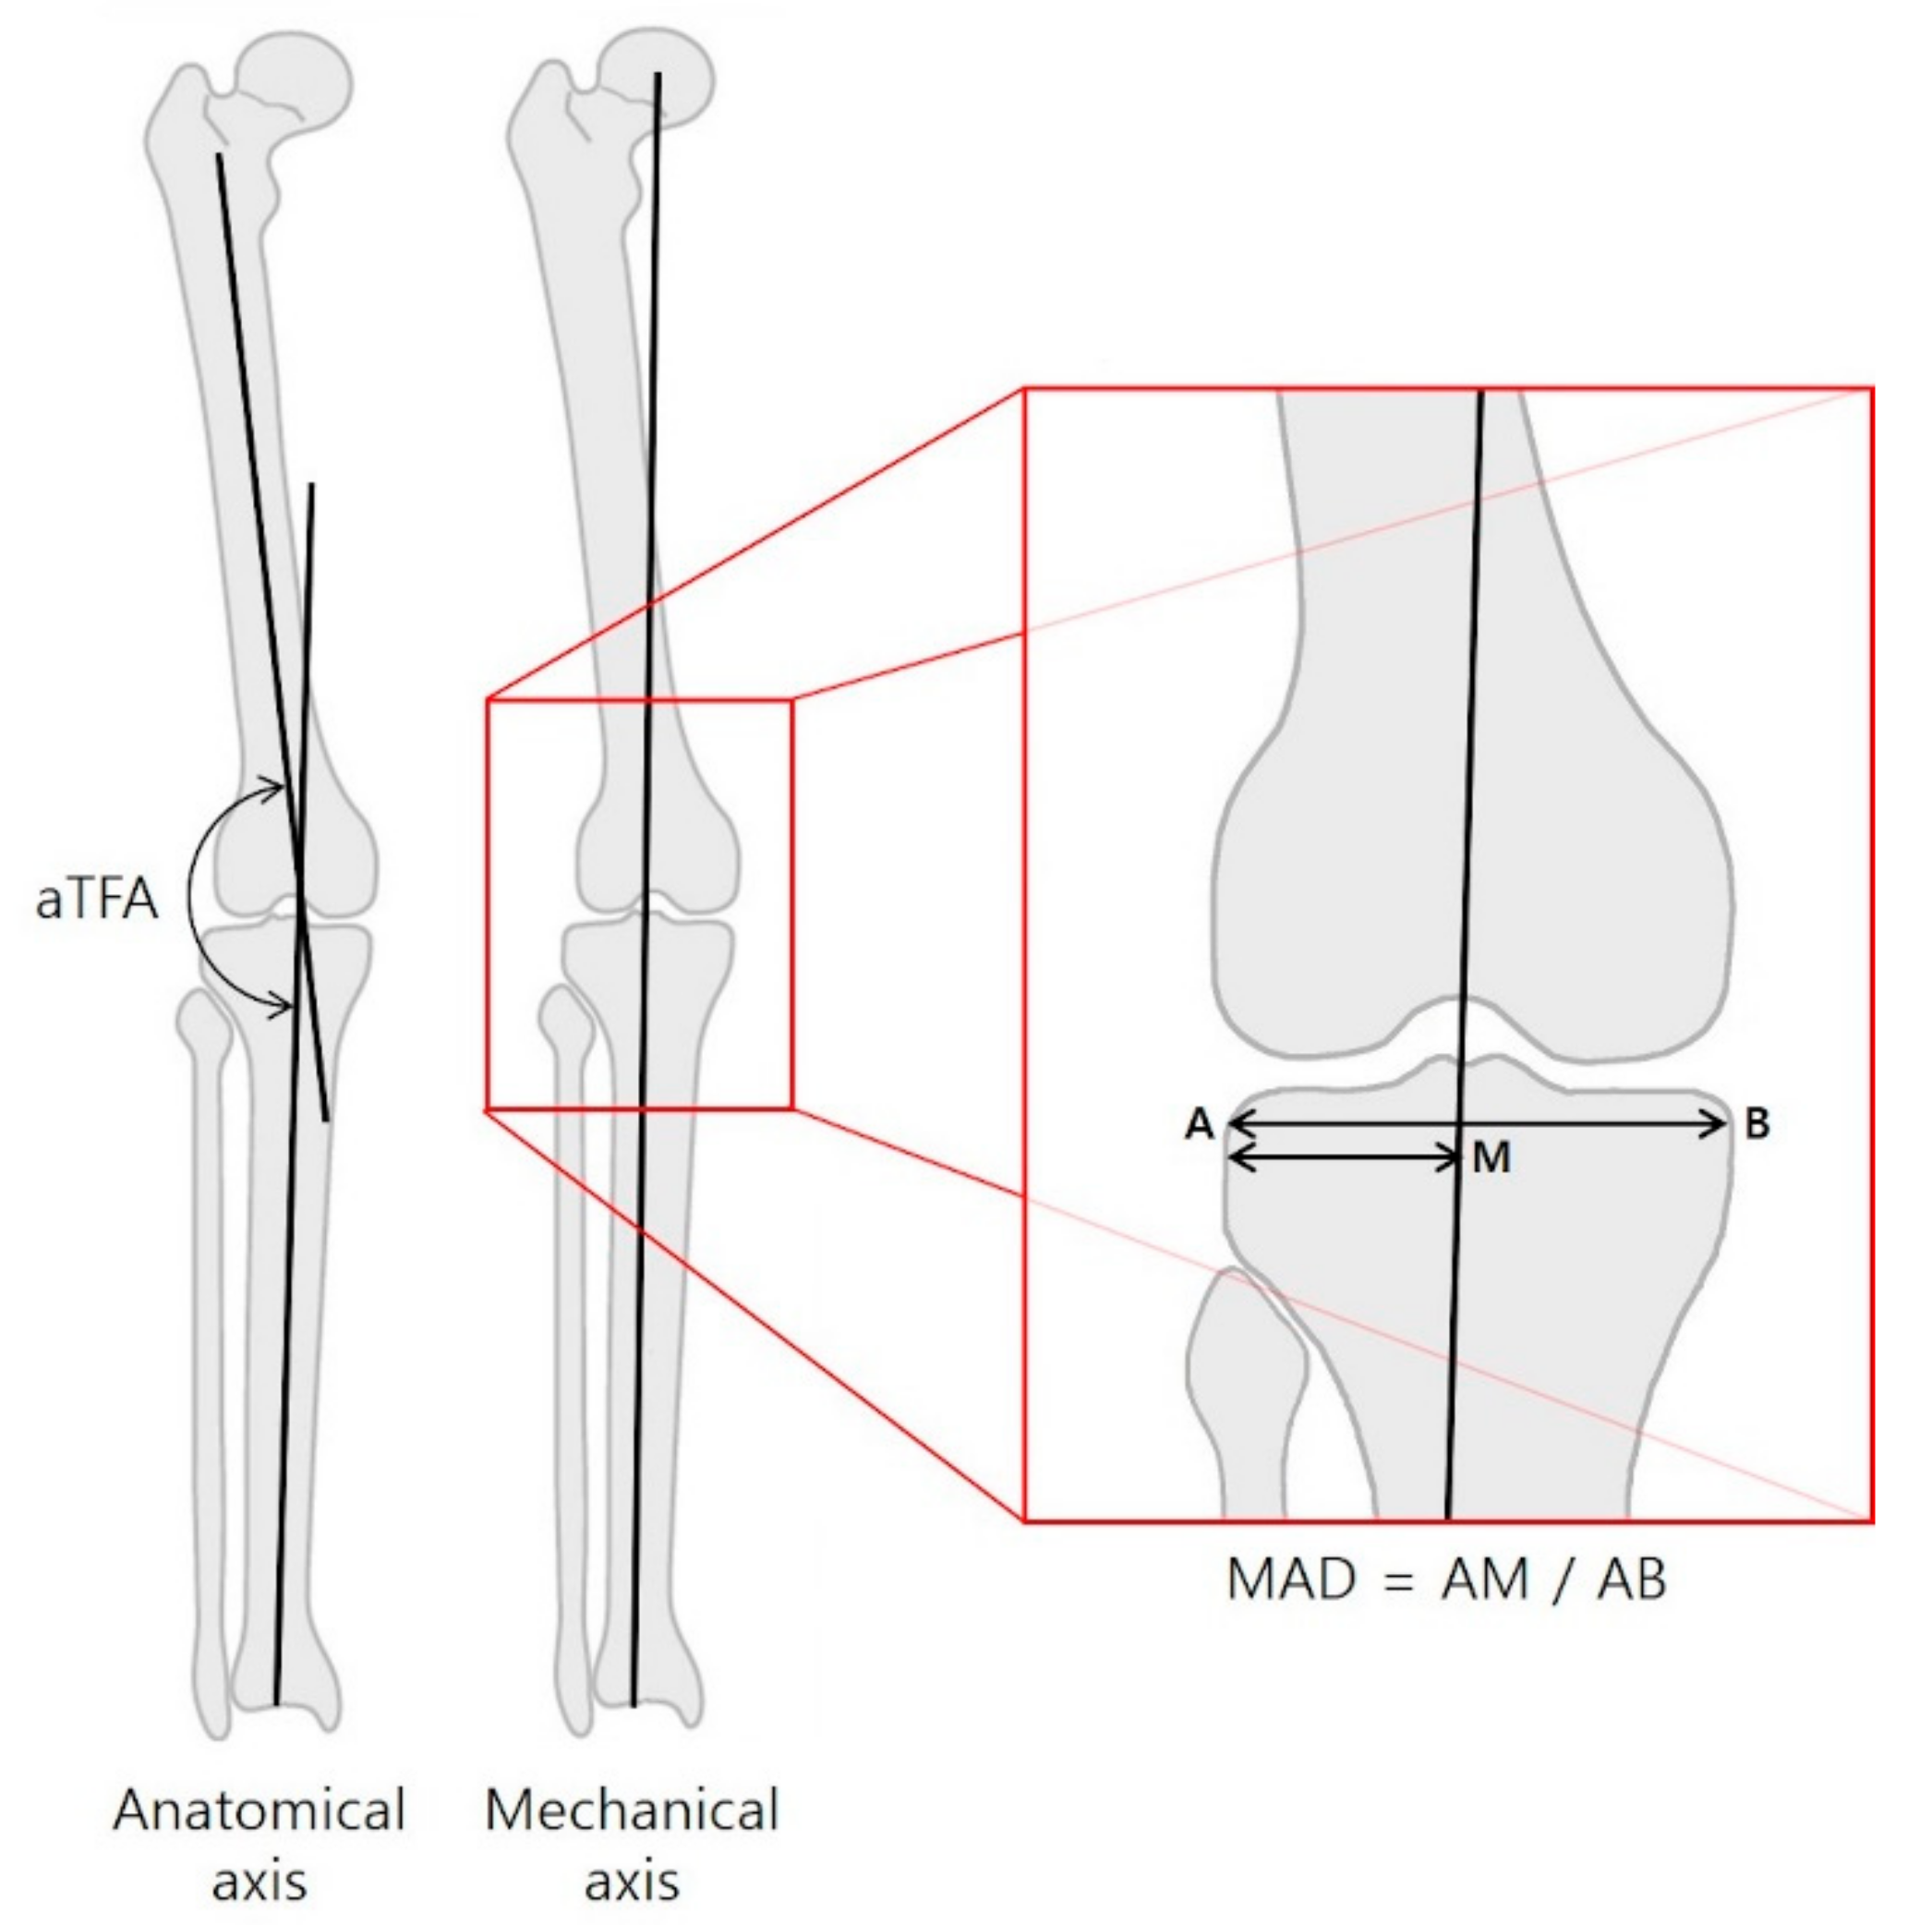

| MAD (ratio) | ||||

| Valgus | 0.32 ± 0.01 | 0.53 ± 0.01 | 0.21 ± 0.02 | <0.001 |

| Varus | 0.78 ± 0.02 | 0.47 ± 0.01 | −0.30 ± 0.03 | <0.001 |